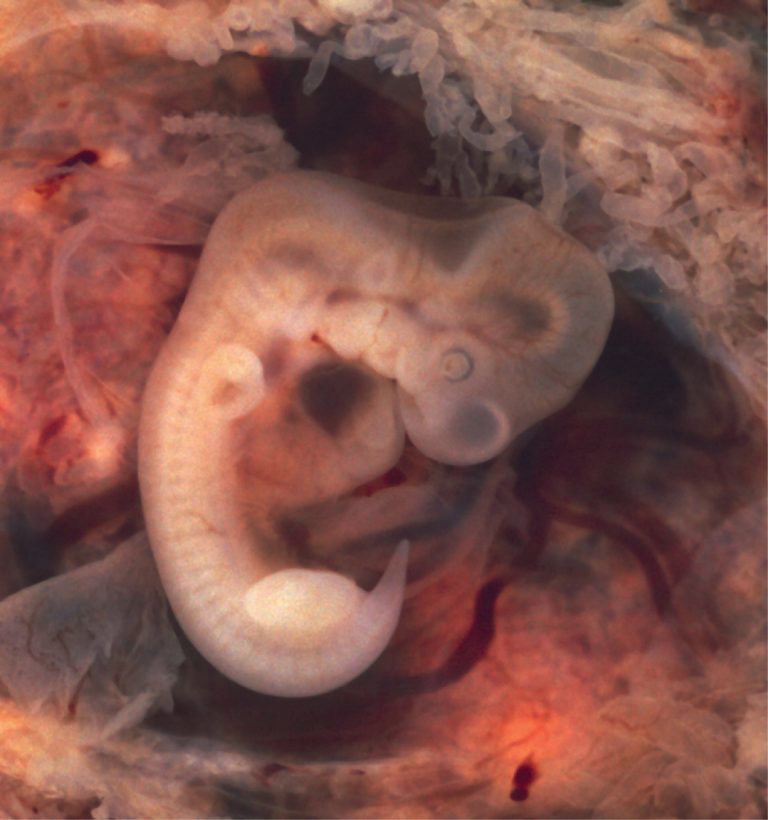

During the sixth week, uncontrolled fetal limb movements begin to occur. The gastrointestinal system develops too rapidly for the embryonic abdomen to accommodate it, and the intestines temporarily loop into the umbilical cord. Paddle-shaped hands and feet develop fingers and toes by the process of apoptosis (programmed cell death), which causes the tissues between the fingers to disintegrate. By week 7, the facial structure is more complex and includes nostrils, outer ears, and lenses (Figure 2.12). By the eighth week, the head is nearly as large as the rest of the embryo’s body, and all major brain structures are in place. The external genitalia are apparent, but at this point, male and female embryos are indistinguishable. Bone begins to replace cartilage in the embryonic skeleton through the process of ossification. By the end of the embryonic period, the embryo is approximately 3 cm (1.2 in) from crown to rump and weighs approximately 8 g (0.25 oz).

Embryo at 7 Weeks

Figure 2.12 – Embryo at 7 Weeks: An embryo at the end of 7 weeks of development is only 10 mm in length, but its developing eyes, limb buds, and tail are already visible. (This embryo was derived from an ectopic pregnancy.) (credit: Ed Uthman)